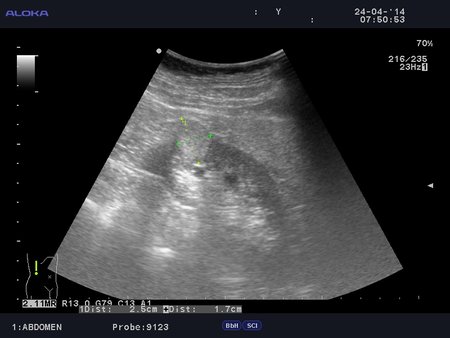

Онкоцитома почки - УЗИ

Женщина 76 лет. Жалоб не предъявляет.

t6_20140424_KIDNEY_0011.JPG

t6_20140424_KIDNEY_0013.JPG